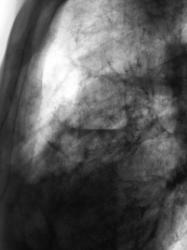

Пациент, при расшифровке флюорограмм, "взят на контроль". Была произведена рентгенография в прямой и боковой проекциях. Пришли к выводу, что имеет место воздушная киста левого лёгкого, содержащая некоторое количество "жидкости".

Согласен с вами. Воздушная киста есть и справа в нижнем поле.

Врожденная патология бронхиального дерева - по типу поликистоза, множественные воздушные кисты и (как говорят студенты) бронхоэкстазы, с признаками активного воспаления...

А может это бронхоэктатическая болезнь?

ИМХО, конечно, но это не похоже на бронхоэктатическую болезнь. Для поликистоза характерно большое колчество кист.